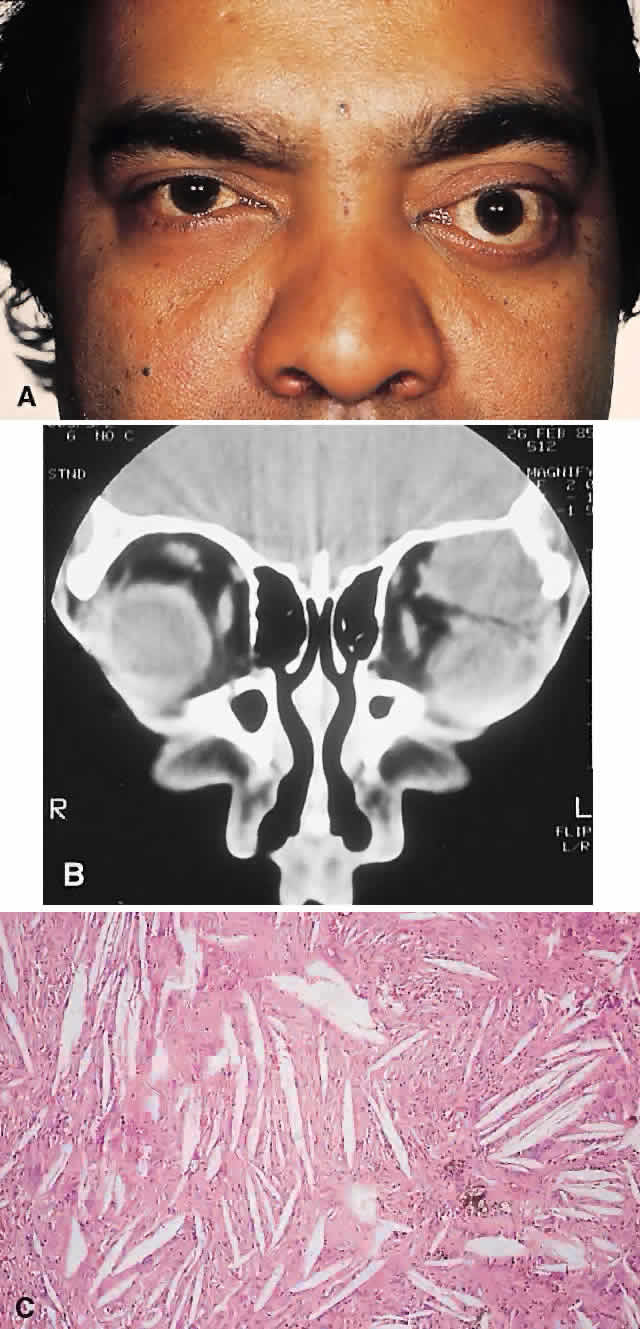

PRESENTATION. The site and the extent of disease are the major determinants of symptomatology. Facial asymmetry, proptosis, and globe displacement evolving over many years are the most common manifestations (Fig. 2). Nasolacrimal duct blockage, diplopia, nasal obstruction, malocclusion, raised intracranial pressure, and cranial nerve palsies also occur.25,28–30 Acute or subacute compressive optic neuropathy can arise as a result of intralesional hemorrhage, sphenoidal mucocele, or secondary aneurysmal bone cyst.31 A more chronic visual loss, although less commonly reported, may occur as a result of compression in the optic canal or at the chiasm. On occasion, a superimposed ischemic neuropathy in the context of chronic compression leads to an acute on chronic deterioration in vision.32

Fig. 2. A. A 20-year-old man presented with a longstanding history of left proptosis and facial asymmetry. B and C. Bone window CT scan showed extensive fibrous dysplasia involving the greater wing of the sphenoid in a sclerotic fashion and a more pagetoid appearance in the maxillary and ethmoidal regions. D and E. Dominant histologic features consisted of irregular trabeculae of woven bone in a fibrous stroma with minimal osteoblastic activity (E) surrounding the osteoid (hematoxylin-eosin; D × 20, E × 50).

This clinical spectrum is reflected in our experience of 10 cases. Changes in facial contour (7 patients), proptosis (7), globe dystopia (6), and decreased vision (3) were the major signs. Interestingly, seven patients also had pain, either localized to the orbit or described as a diffuse ipsilateral headache.

HISTOPATHOLOGY. Macroscopically, fibrous dysplasia consists of gritty, white-to-pink tissue, often with blood or serous-filled cystic areas. Histologically, there is a fibrous background containing trabeculae of woven bone. The stroma has variable amounts of collagen, fibroblasts, and vascularity. There may also be myxomatous areas and secondary aneurysmal bone cysts. The curvilinear bone trabeculae take on a variety of configurations, including C or Y shapes (so-called Chinese characters). These trabeculae sometimes have irregular margins as a result of the attachment of collagen fibers arising in the stroma. Cartilaginous nodules as well as small foci of lamellar bone are occasionally seen, but the vast majority of lesions contain immature woven bone. At its periphery, fibrous dysplasia permeates normal bone, and there may be areas of reactive bone with more prominent lamellar bone formation and osteoblastic rimming. Sequential biopsies of fibrous dysplasia from childhood to adult life have shown that the histologic picture does not change with time.36